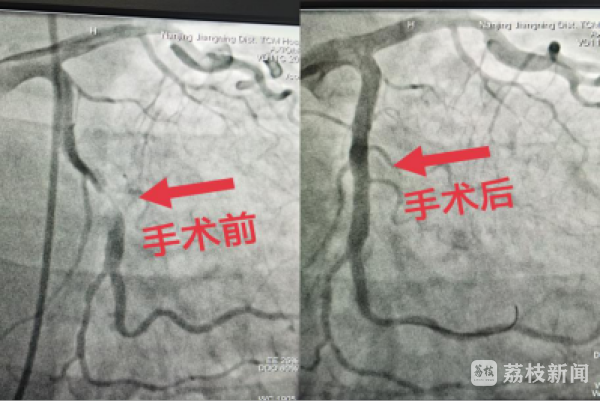

3月22日晚10点,家住封控区内51岁的刘先生突发胸痛6小时,被紧急送往江宁中医院急诊科就诊。急诊科医生接诊后急查心电图提示“心肌缺血”,经心内科韦锋主任紧急会诊后考虑为“急性非ST段抬高型心肌梗死”。患者由于病情危重,立即被收入重症医学中心监护治疗。因患者胸痛仍持续不缓解,为减少心肌坏死面积,韦主任决定立即进行急诊冠状动脉造影和支架植入术。

接到手术通知后,心内科徐佳杨、魏文波医生、成婷护士以及刚下班的郭良玉医生立刻赶到工作岗位,大家齐心协力,密切配合,完成各项术前准备,克服穿戴防护服和铅衣带来的操作不便,凭借过硬的技术和丰富的经验,历时80余分钟,顺利完成手术,患者平安返回病房。

这是江宁区集中医疗救治中心迎来的第一台心脏介入手术。手术结束后,医护人员的防护服和铅衣上布满了汗水,但是看到患者各项体征指标趋于平稳,胸痛症状得以缓解,他们都露出了欣慰的笑容。